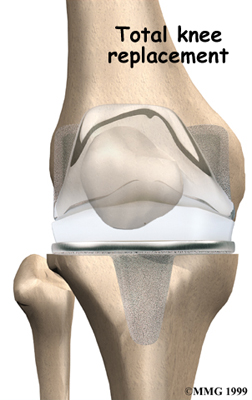

Artificial Knee Replacement

An artificial knee replacement is the ultimate solution for advanced knee OA.

Surgeons prefer not to put a new knee joint in patients younger than 60. This is because younger patients are generally more active and might put too much stress on the joint, causing it to loosen or even crack. A revision surgery to replace a damaged prosthesis is harder to do, has more possible complications, and is usually less successful than a first-time joint replacement surgery.

Related Document: FYZICAL Edina's Guide to Artificial Joint Replacement of the Knee